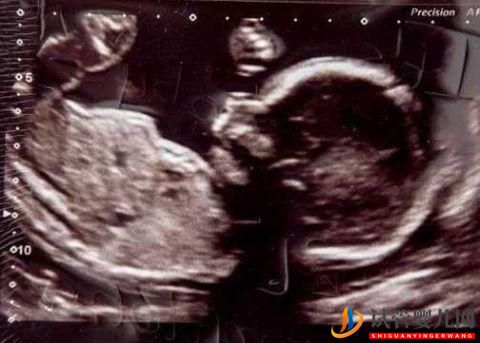

借了利率高達(dá)49.9%的現(xiàn)金貸,未來五年他們倆必須償還£23,715的現(xiàn)金。作為NHS的管理者的Carolyn,找到了現(xiàn)金貸公司Amigo,給她資助了六輪試管受精費(fèi)用。令她高興的是,她懷孕了并將于下個(gè)月生下一個(gè)名叫Kayleigh的女兒。“我一點(diǎn)也不后悔。如果不是貸款,我現(xiàn)在都不會(huì)懷孕”